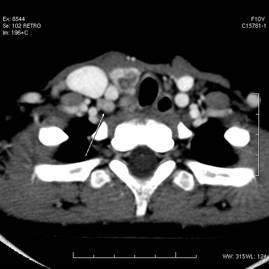

1、砂粒样甲状腺结节钙化,甲状腺结节钙化几乎为甲状腺恶性肿瘤所共有,甲状腺结节钙化常是乳头状腺恶变的特征性表现。

2、粗大的甲状腺结节钙化影像中,约有10%~20%为恶变,其中滤泡状腺恶变所占比例大。

3、髓样恶变常粗大颗粒和砂粒样钙化相混合。

4、一般甲状腺良性肿瘤钙化影像多致密,边缘清楚,而恶性肿瘤则阴影淡而模糊。

医师提醒:如果B超检查结果显示甲状腺结节有钙化,那么B超单上可能还显示有结节边界不清,边缘模糊,低回声等描述。临床上对出现上述特征的结节可初步诊断为恶性结节。